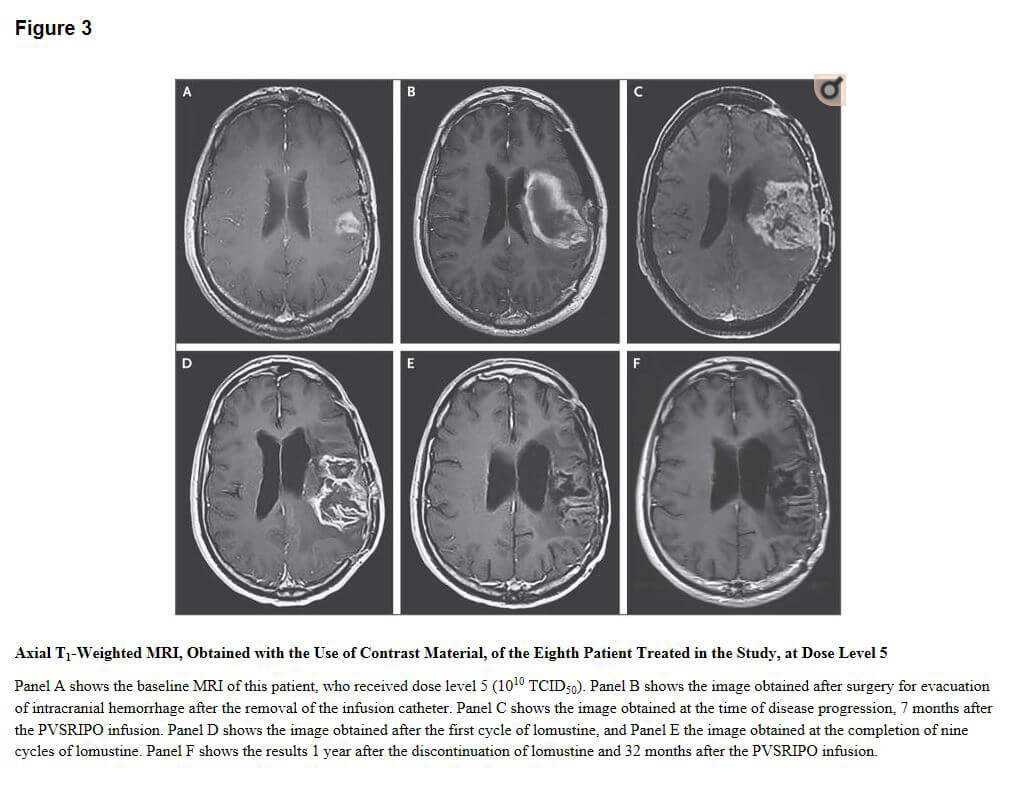

Recurrent Glioblastoma Treated with Recombinant Polio virusFigure 3 credit: Desjardins A, Gromeier M, Herndon JE 2nd, et al. Recurrent Glioblastoma Treated with Recombinant Poliovirus. N Engl J Med. 2018;379(2):150–161. doi:10.1056/NEJMoa1716435.